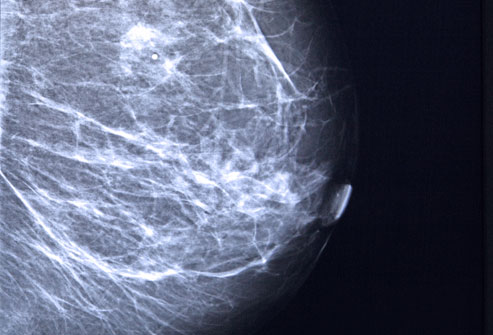

- การตรวจเต้านมด้วย แมมโมแกรม ซึ่งจัดว่าเป็นวิธีที่ดีที่สุดในการตรวจคัดกรอง มะเร็งเต้านมในผู้หญิงทั่วไป

- แมมโมแกรม (Mammogram) การถ่ายภาพรังสีเต้านมเพื่อหาจุดผิดปกติ